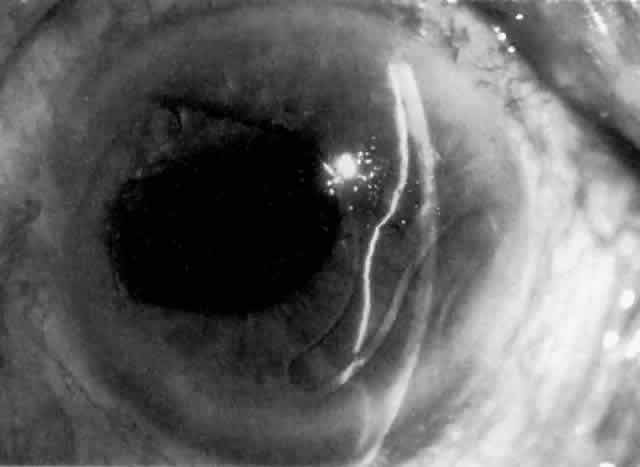

IOL-related inflammation is more commonly associated with some styles of lens implants than with others. Position of the lens or foreign material deposited on the lens during manufacture can also account for persistent inflammation. When the inflammation is associated with hyphema, it is termed UGH syndrome, which involves the triad of uveitis, glaucoma, and hyphema. UGH syndrome occurred more frequently in the 1970s, when iris-fixed lenses were commonly used.66,67 Today it is more often associated with anterior chamber lenses and is less likely to occur with posterior chamber lenses, although this has been reported.68,69 The mechanism is believed to be contact of the surface of the lens with the iris, causing mechanical irritation that may be enhanced by a poorly positioned or mobile lens implant. The loose posterior chamber lens may initially exhibit release of pigment due to friction on the posterior surface of the iris (pseudopigmentary glaucoma). This “windshield-wiper” effect alone can produce enough pigment to provoke an increase in IOP; however, it is the erosion into vascular tissue that results in hemorrhage, hyphema, and inflammation (Figs. 4 and 5).

As mentioned in the Persistent Inflammation section, pseudopigmentary glaucoma is in many ways similar to the persistent inflammation that results from an IOL implant. The mechanism is believed to be contact of the surface of the lens with the iris. In persistent inflammation and UGH syndrome, typically either an anterior chamber lens or an iris-fixed lens is the culprit. With respect to pseudopigmentary glaucoma, however, the lens used is more likely to be a posterior chamber lens with the haptics (either one or both) positioned in the sulcus. In this way, the pigmented surface of the iris moves back and forth across the edge of the IOL, promoting release of pigment into the anterior chamber (see Figs. 4 and 5). The mechanism of IOP elevation is outflow obstruction from the excessive amounts of pigment granules and cell debris in the trabecular meshwork.